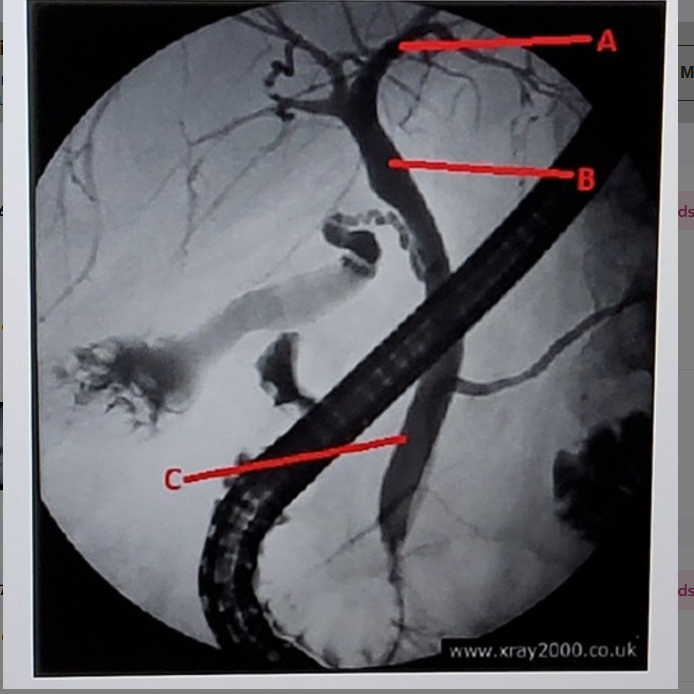

common bile duct

what is letter C